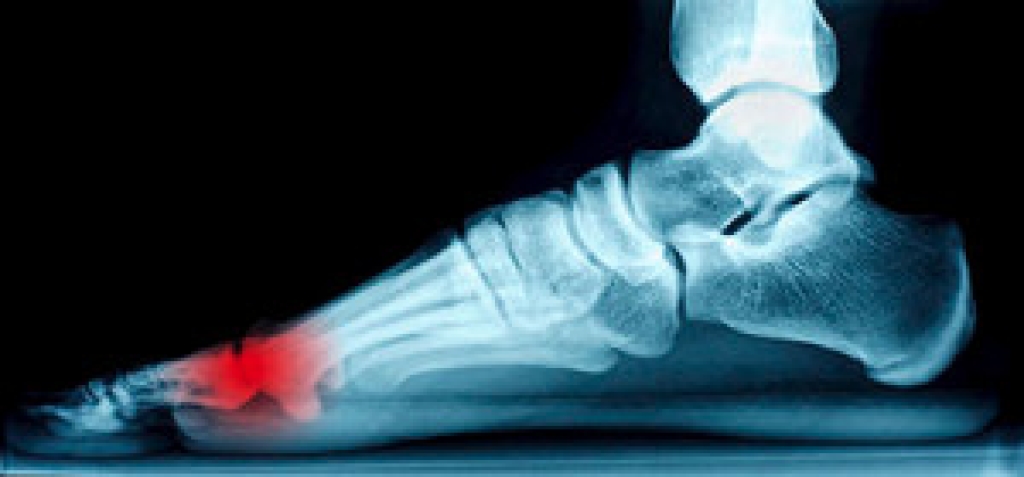

Our feet endure pressure during the majority of the day. It is important to promptly treat existing cuts or bruises on the feet, as this may be helpful in preventing foot wounds from developing. Patients who may be susceptible to developing wounds on the feet can include people who are diabetic or have medical conditions consisting of elevated cholesterol and blood pressure. It is beneficial to wear shoes and socks that are comfortable, in addition to trimming the toenails properly. A wound on the foot will heal faster when treated quickly, and it is strongly advised that you speak with a podiatrist who can effectively treat foot wounds.

While it may not seem apparent with small ulcers on the foot, for diabetics, any size ulcer can become infected. Diabetics often also suffer from neuropathy, or nerve loss. This means they might not even feel when they have an ulcer on their foot. If the wound becomes severely infected, amputation may be necessary. Therefore, it is of the upmost importance to properly care for any and all foot wounds.

The best way to care for foot wounds is to prevent them. For diabetics, this means daily inspections of the feet for any signs of abnormalities or ulcers. It is also recommended to see a podiatrist several times a year for a foot inspection. If you do have an ulcer, run the wound under water to clear dirt from the wound; then apply antibiotic ointment to the wound and cover with a bandage. Bandages should be changed daily and keeping pressure off the wound is smart. It is advised to see a podiatrist, who can keep an eye on it.